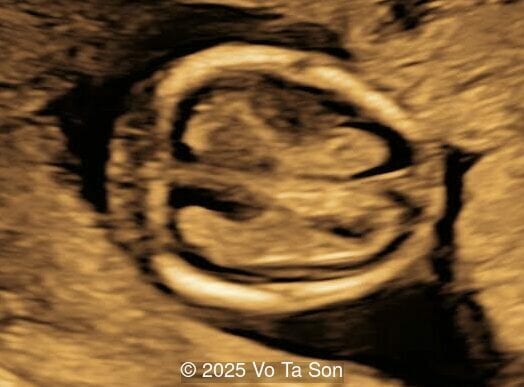

- Open spina bifida in the sacral region with dry brain and crash sign, BS/BSOB >1, direct lesion at sacral coccygeal spine